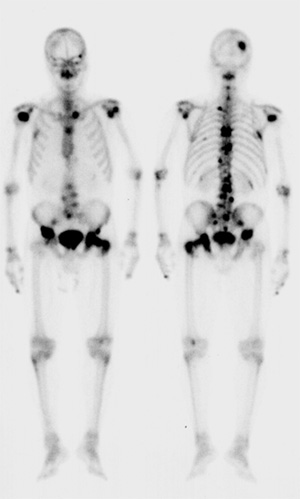

全身骨シンチグラフィ 乳癌 肺癌 前立腺癌等の骨転移病巣の検出

全身骨シンチグラフィ 乳癌 肺癌 前立腺癌等の骨転移病巣の検出

骨シンチグラフィによる骨転移の診断 Bone Scan Ct Mri画像診断